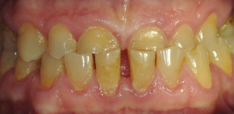

ДО

Пациент обратился с жалобой на истирание передней и боковой групп зубов, отсутствие жевательных зубов, затрудненное пережевывание пищи, ухудшение дикции, появление морщин в уголках рта.